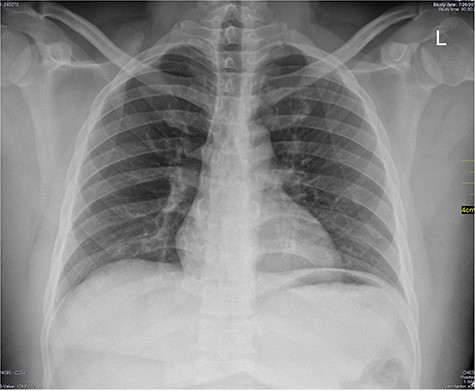

Chest X-ray was normal as shown in Fig. 1. Focused abdominal sonography for trauma (FAST) scan showed mild left perihepatic collection necessitating a thoracoabdominal computerized tomography (CT)-scan which showed external oblique muscle laceration with intermuscular air lucencies and grade 2 hepatic injury as shown in Figs 2–4. Other blood work-up were normal. No other injury was found on secondary survey. His wound was explored under local anaesthesia, primarily repaired, and he was discharged after 24 h of close observation.

Image shows lucent air densities tracking through the subcapsular haematoma in the left lobe of the liver anterior to the pylorus of the stomach.